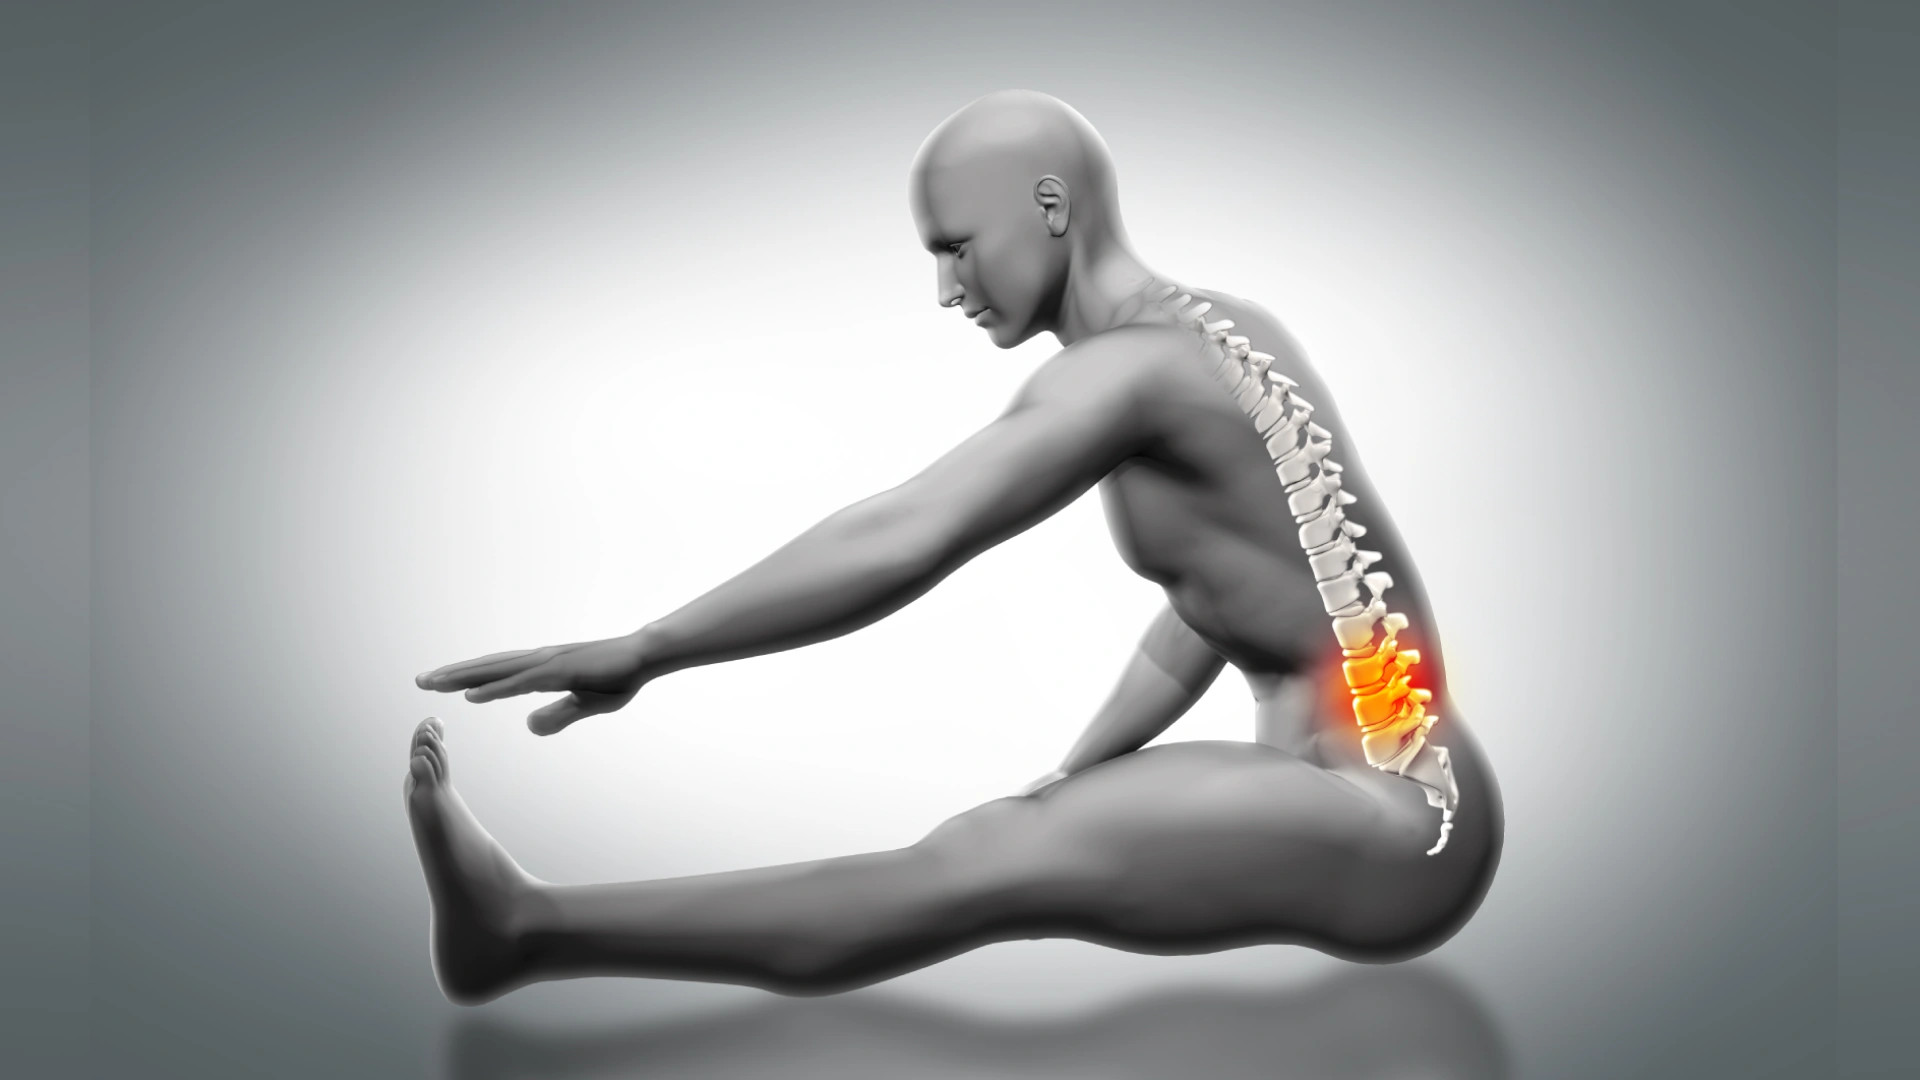

Movement is something most of us take for granted—until it changes. A movement disorder refers to a group of neurological conditions that disrupt the normal control of physical actions, resulting in movements that are either too fast, too slow, involuntary, or poorly coordinated. These conditions can affect daily life, independence, and emotional well-being.

Movement disorders are conditions that arise when parts of the nervous system—including the brain, spinal cord, and peripheral nerves—do not communicate properly with the muscles that control movement. They may cause:

How Do Movement Disorders Affect the Body?

Every voluntary movement—walking, talking, writing—depends on a tightly controlled network of signals from the brain to the muscles and back. Movement disorders disrupt this system, often due to:

3. Dystonia

Characterized by sustained muscle contractions that cause twisting, repetitive movements, or abnormal postures. It may affect one body part (focal dystonia) or be more widespread.